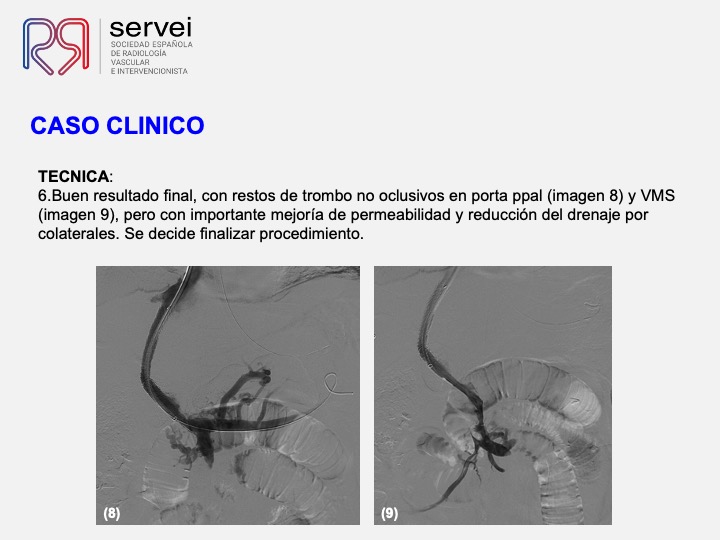

- Isquemia mesenterica venosa 01

- Isquemia mesenterica venosa 02

- Isquemia mesenterica venosa 03

- Isquemia mesenterica venosa 04

- Isquemia mesenterica venosa 05

- Isquemia mesenterica venosa 06

- Isquemia mesenterica venosa 07

- Isquemia mesenterica venosa 08

- Isquemia mesenterica venosa 09

- Isquemia mesenterica venosa 10

- Isquemia mesenterica venosa 11